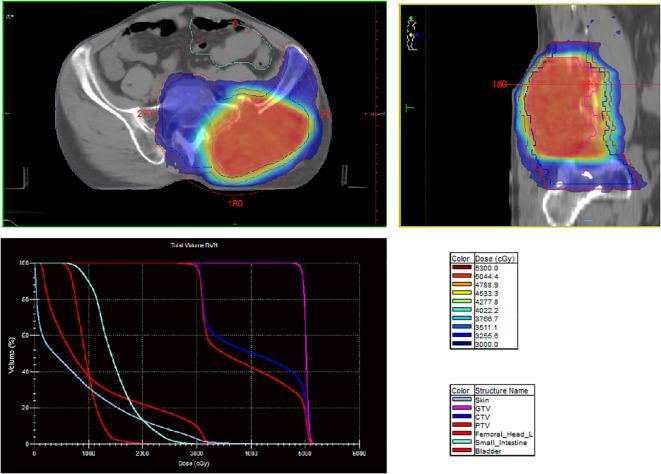

臀中肌转移的肝细胞癌治疗:1例病例报告及文献复习

Treatment of hepatocellular carcinoma with gluteus medius metastasis: a case report and a literature review.

Hepatocellular carcinoma (HCC) accounts for 85%-90% of all primary liver cancers (PLCs). Owing to the occult nature of HCC, most patients present at an advanced stage at the time of initial diagnosis and have a poor prognosis. With regard to systemic therapy, targeted therapy and immunotherapy are currently the centers of clinical research. With regard to local treatment, surgical resection, radiofrequency ablation, hepatic artery chemoembolization, and radiotherapy are commonly used. Interstitial brachytherapy is commonly used for the treatment of cervical and genitourinary cancers. In this case, interstitial brachytherapy was used to treat gluteus medius muscle metastasis from PLC, with good local control and symptom relief.

摘要

肝细胞癌(HCC)占所有原发性肝癌(PLC)的85%-90%。由于HCC具有隐匿性,大多数患者在初诊时已处于晚期,预后较差。在全身治疗方面,靶向治疗和免疫治疗是目前临床研究的重点。在局部治疗方面,手术切除、射频消融、肝动脉化疗栓塞和放射治疗是常用的方法。间质近距离放射治疗常用于治疗宫颈癌和泌尿生殖系统癌症。在本病例中,间质近距离放射治疗被用于治疗PLC的臀中肌转移,局部控制良好,症状得到缓解。